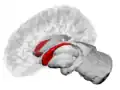

The caudate nuclei are near the center of the brain, sitting astride the thalamus. There is a caudate nucleus in each hemisphere of the brain. Each nucleus is C-shaped, with a wider "head" (caput in Latin) at the front, tapering to a "body" (corpus) and a "tail" (cauda). Sometimes a part of the caudate nucleus is called the "knee" (genu).[6] The caudate head receives its blood supply from the lenticulostriate artery; the tail of the caudate receives its blood supply from the anterior choroidal artery.[7]

The head and body of the caudate nucleus form part of the floor of the anterior horn of the lateral ventricle. The body travels briefly towards the back of the head; the tail then curves back toward the anterior, forming the roof of the inferior horn of the lateral ventricle. This means that a coronal section (on a plane parallel to the face) that cuts through the tail will also cross the body and head of the caudate nucleus.